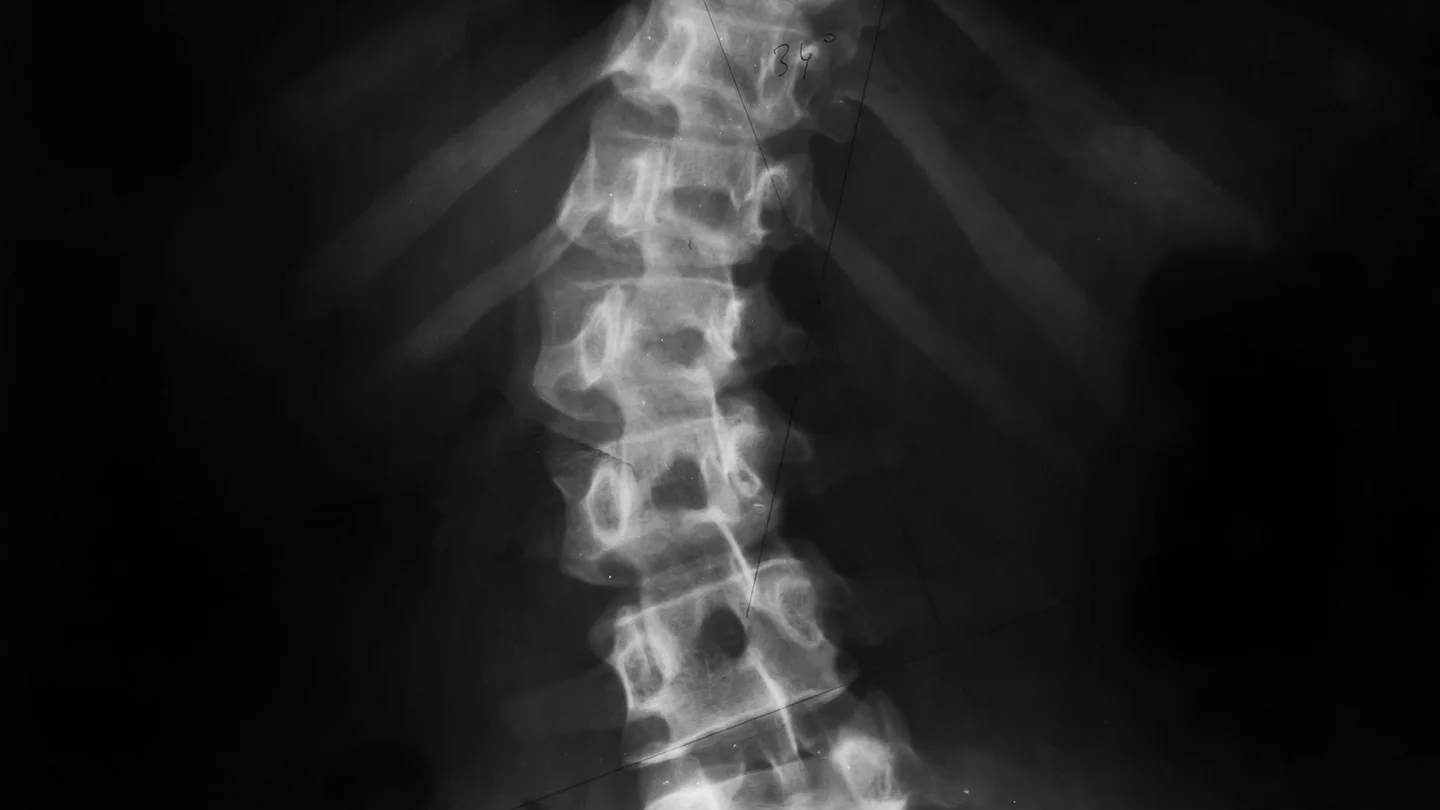

Die Wirbelsäule kann bei einer Skoliose unterschiedlich stark verkrümmt sein. Der Grad der Verkrümmung wird als Cobb-Winkel bezeichnet und mit einem Röntgenbild bestimmt.

- Röntgenbild der Wirbelsäule im Stehen: Das Bild zeigt, wie stark die Krümmung ist, und dient zur Ermittlung des Cobb-Winkels.